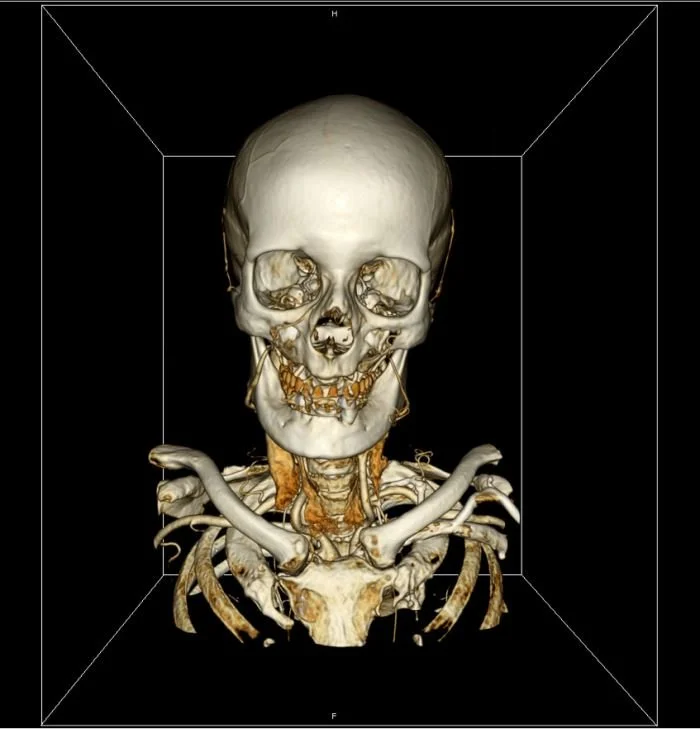

Стандарт позволяет организовать цифровую связь между различным диагностическим и терапевтическим оборудованием, использующимся в системах различных производителей. Рабочие станции, Компьютерные (КТ) и Магнитно-резонансные Томографы (МРТ), микроскопы, УЗ-сканеры, общие архивы, хост-компьютеры и мэйнфреймы от разных производителей, расположенные в одном городе или нескольких городах, могут "общаться" друг с другом на основе DICOM с использованием открытых сетей по стандартным протоколам, например TCP/IP.

Популярные программы для просмотра DICOM-файлов (Windows, macOS, iOS, Android и Linux)

Видео-обзор лучших программ для просмотра DICOM-файлов

CT — Компьютерная томография (Computed Tomography)